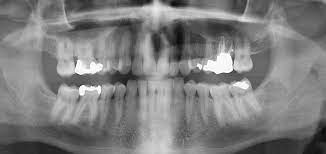

During a dental conference, Dr. Meera was introduced to OPG dental imaging, a technology designed to capture panoramic views of the entire mouth in a single image. She learned how OPG could reveal details that traditional methods couldn’t, offering a clearer understanding of complex dental structures.

Excited about the potential, Dr. Meera decided to integrate OPG imaging into her practice. The results were transformative. With OPG, she could finally pinpoint the cause of Rohan’s jaw pain—a hidden dental cyst that had gone unnoticed. Thanks to the precise imaging, Dr. Meera was able to develop an effective treatment plan, alleviating Rohan’s pain and restoring his trust in her care.

To illustrate the product’s effectiveness, consider the case of another dentist, Dr. Rajesh from Chennai. Faced with a similar diagnostic challenge involving a young patient with unexplained facial swelling, Dr. Rajesh turned to OPG imaging. The panoramic view revealed an impacted wisdom tooth pressing against the nerve, which was missed in regular X-rays. The early and accurate diagnosis allowed Dr. Rajesh to perform a successful surgery, saving the patient from potential complications.